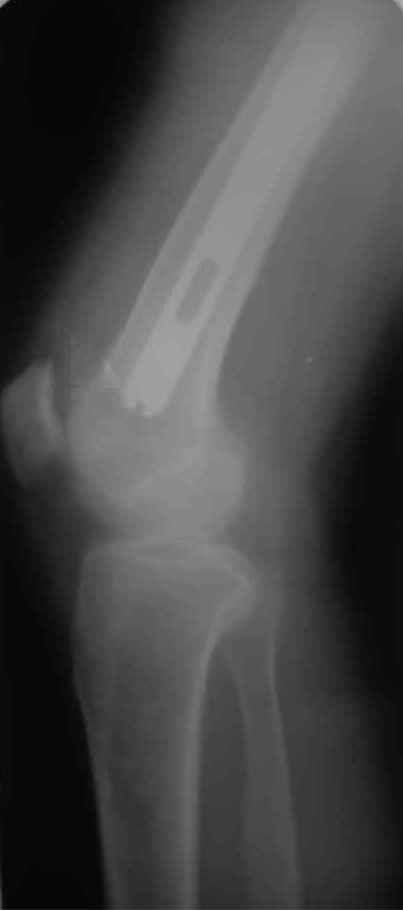

Re: Перипротезный перелом

новые снимки